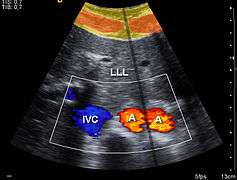

Doppler ultrasonography is used to study blood flow and muscle motion. The different detected speeds are represented in color for ease of interpretation, for example leaky heart valves: the leak shows up as a flash of unique color. Colors may alternatively be used to represent the amplitudes of the received echoes.

- Color Doppler: Velocity information is presented as a color-coded overlay on top of a B-mode image

Sonography can be enhanced with Doppler measurements, which employ the Doppler effect to assess whether structures (usually blood)[16] are moving towards or away from the probe, and its relative velocity. By calculating the frequency shift of a particular sample volume, for example flow in an artery or a jet of blood flow over a heart valve, its speed and direction can be determined and visualised. This is particularly useful in cardiovascular studies (sonography of the vascular system and heart) and essential in many areas such as determining reverse blood flow in the liver vasculature in portal hypertension. The Doppler information is displayed graphically using spectral Doppler, or as an image using color Doppler (directional Doppler) or power Doppler (non directional Doppler). This Doppler shift falls in the audible range and is often presented audibly using stereo speakers: this produces a very distinctive, although synthetic, pulsating sound.

It should be noted here that there are no standards for the display of color Doppler. Some laboratories show arteries as red and veins as blue, as medical illustrators usually show them, even though some vessels may have portions flowing towards and portions flowing away from the transducer. This results in the illogical appearance of a vessel being partly a vein and partly an artery. Other laboratories use red to indicate flow toward the transducer and blue away from the transducer. Still other laboratories prefer to display the sonographic Doppler color map more in accord with the prior published physics with the red shift representing longer waves of echoes (scattered) from blood flowing away from the transducer; and with blue representing the shorter waves of echoes reflecting from blood flowing toward the transducer. Because of this confusion and lack of standards in the various laboratories, the sonographer must understand the underlying acoustic physics of color Doppler and the physiology of normal and abnormal blood flow in the human body (see Red shift[17][18][19]).